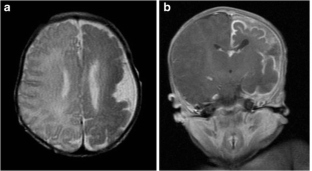

Pre- and postnatal imaging of early cerebral damage in Sturge-Weber syndrome

A case of prenatal diagnosis of Sturge-Weber syndrome associated with polymicrogyria is reported. The diagnosis was based on a unique association with unilateral hemispheric gyriform calcification, focal hemispheric atrophy and white matter changes on prenatal imaging including ultrasound and MRI. Polymicrogyria, which is exceptionally associated with Sturge-Weber syndrome, is suggestive of and reinforces the hypothesis of early impairment of the cerebral microvasculature related to leptomeningeal angioma, which may lead to abnormal cerebral development as early as the second trimester of pregnancy.

Fig. 1

Fig. 2